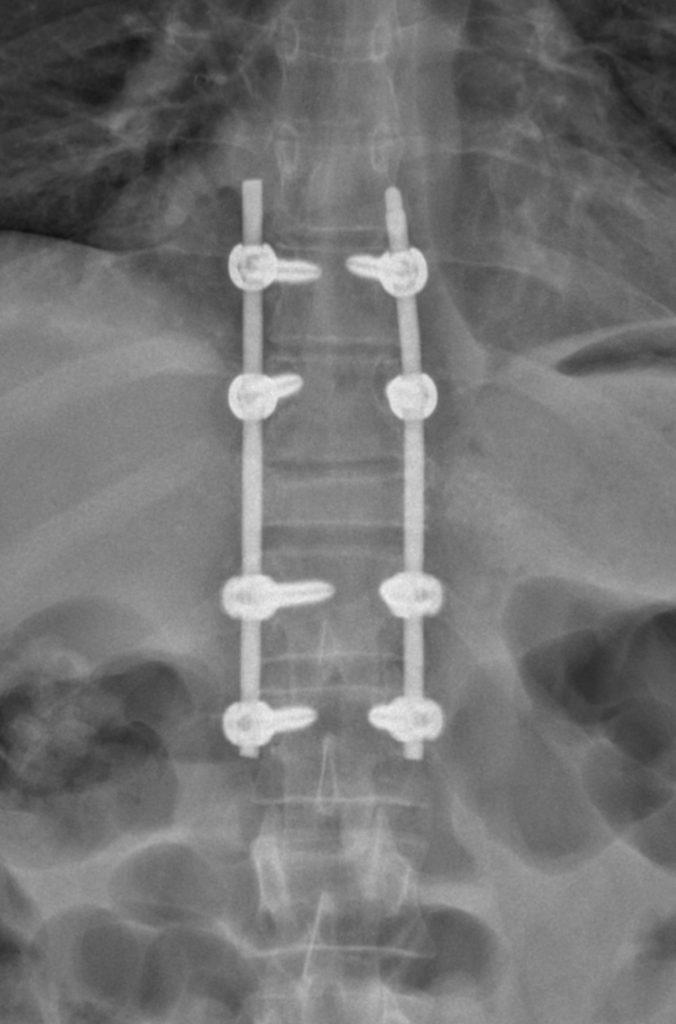

In May 2022, Dr. Hughes performed a T9-L1 fusion and T11 osteotomy, removing the kyphotic angulation from my damaged vertebra. I haven't felt any pain in my back since.